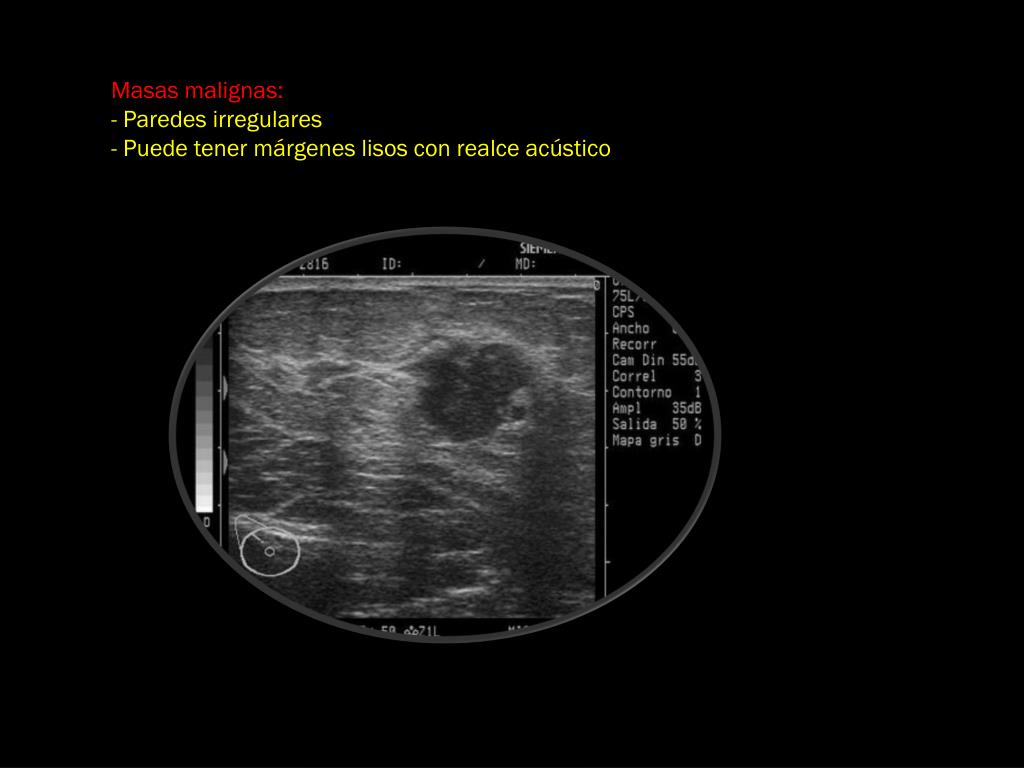

25. Masas malignas: - Paredes irregulares - Puede tener márgenes lisos con realce acústico